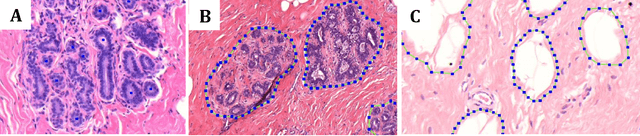

Abstract:Terminal ductal lobular unit (TDLU) involution is the regression of milk-producing structures in the breast. Women with less TDLU involution are more likely to develop breast cancer. A major bottleneck in studying TDLU involution in large cohort studies is the need for labor-intensive manual assessment of TDLUs. We developed a computational pathology solution to automatically capture TDLU involution measures. Whole slide images (WSIs) of benign breast biopsies were obtained from the Nurses' Health Study (NHS). A first set of 92 WSIs was annotated for TDLUs, acini and adipose tissue to train deep convolutional neural network (CNN) models for detection of acini, and segmentation of TDLUs and adipose tissue. These networks were integrated into a single computational method to capture TDLU involution measures including number of TDLUs per tissue area, median TDLU span and median number of acini per TDLU. We validated our method on 40 additional WSIs by comparing with manually acquired measures. Our CNN models detected acini with an F1 score of 0.73$\pm$0.09, and segmented TDLUs and adipose tissue with Dice scores of 0.86$\pm$0.11 and 0.86$\pm$0.04, respectively. The inter-observer ICC scores for manual assessments on 40 WSIs of number of TDLUs per tissue area, median TDLU span, and median acini count per TDLU were 0.71, 95% CI [0.51, 0.83], 0.81, 95% CI [0.67, 0.90], and 0.73, 95% CI [0.54, 0.85], respectively. Intra-observer reliability was evaluated on 10/40 WSIs with ICC scores of >0.8. Inter-observer ICC scores between automated results and the mean of the two observers were: 0.80, 95% CI [0.63, 0.90] for number of TDLUs per tissue area, 0.57, 95% CI [0.19, 0.77] for median TDLU span, and 0.80, 95% CI [0.62, 0.89] for median acini count per TDLU. TDLU involution measures evaluated by manual and automated assessment were inversely associated with age and menopausal status.